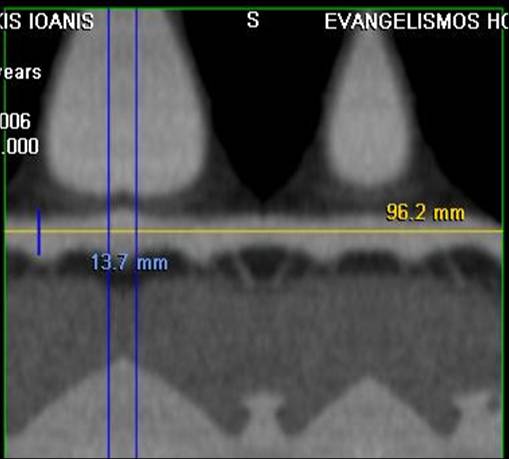

The non-invasive imaging modality of multi-detector computed tomography has dramatically evolved the last ten years and that is due to hardware and software developments. The newer generation of scanners allows increased spatial and temporal resolution that improves the clinical reliability giving further insights into the evaluation of coronary artery disease. Heart morphology imaging followed by studies of myocardial function and assessment of cardiac valves can be performed from the information derived from the data of the coronary artery examination. Also, the venous anatomy of the heart, coronary artery bypass grafts, stents, and cardiac tumors can be imaged and evaluated when necessary. For the beneficial use of this method, entrance criteria for different patient groups need to be set in order to allow improved outcome of multi-detector CT.